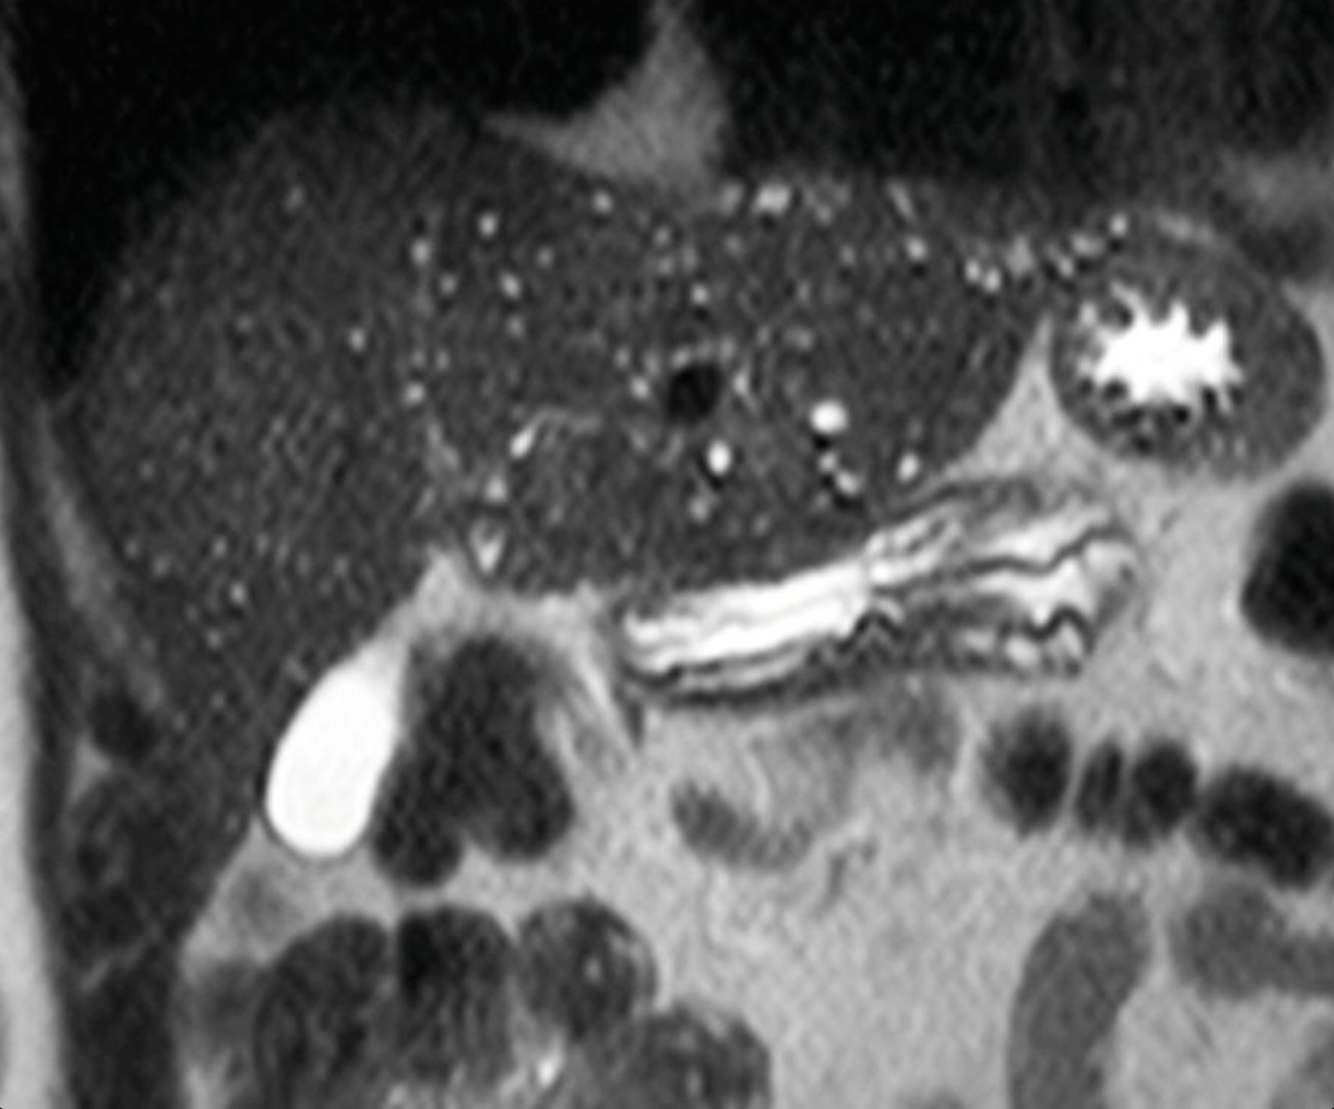

These splenic findings are most commonly associated w/what process?

Gamna-Gandy bodies = PHTN.